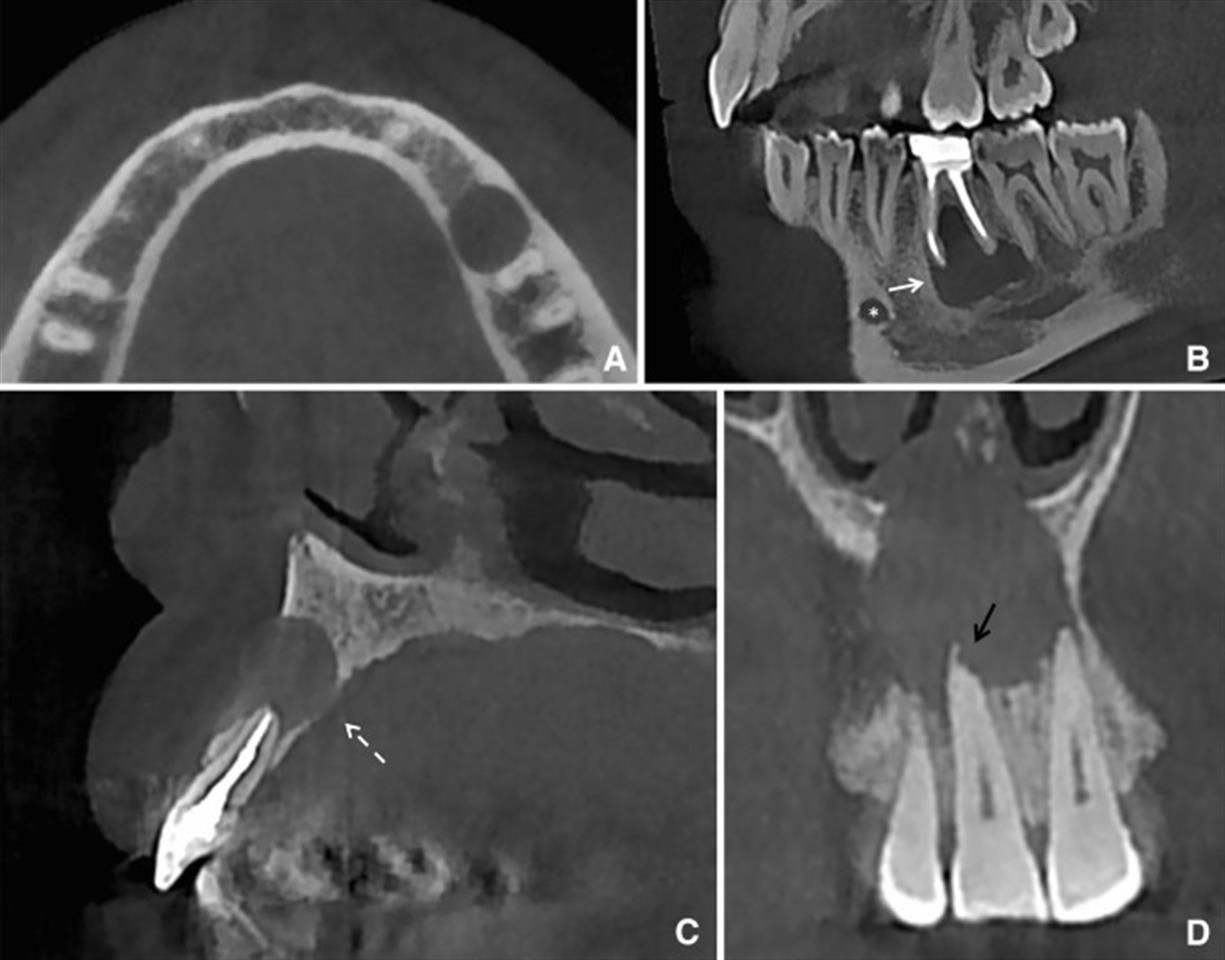

From www.researchgate.net

(AB) The eVol DX CBCT images showing tooth 36 with detailed Dental Cbct Interpretation learn how to interpret cone beam computed tomography (cbct) scans for endodontic diagnosis and treatment planning. Find out how to select the. learn the fundamentals of radiographic interpretation for dental diagnosis and treatment planning. learn about the principles and practices for safe and appropriate use of cbct in oral and maxillofacial radiology. learn how to interpret. Dental Cbct Interpretation.